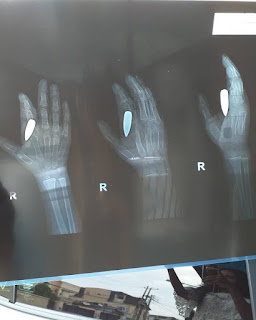

Artist Uche Novia, reviews how a stray bullet got stock in his son’s hand for 28 days without his knowledge.

Okay y'all must have seen me post one or two things about my boy, Rocky. The incident happened on the 7th of February, I just got back from work when I heard him scream so loud. I rushed out and saw him crying and holding his right hand. We all thought something had cut his hand maybe while he was playing with the cup he was using to drink water. We rushed him to a local Bone doctor close to the house. The man did his best to adjust the bone and asked us to wait till the wound heals then we can come to fix the bone properly. All these while we thought we were treating bone. Not until few days ago we decided to do a scan and we found out a stray bullet almost hit this boy somewhere else but instead of hitting somewhere else, it hit his hand. We just did a minor surgery yesterday and a bullet was taken out. It could only be God. God did this for us and we are forever grateful.